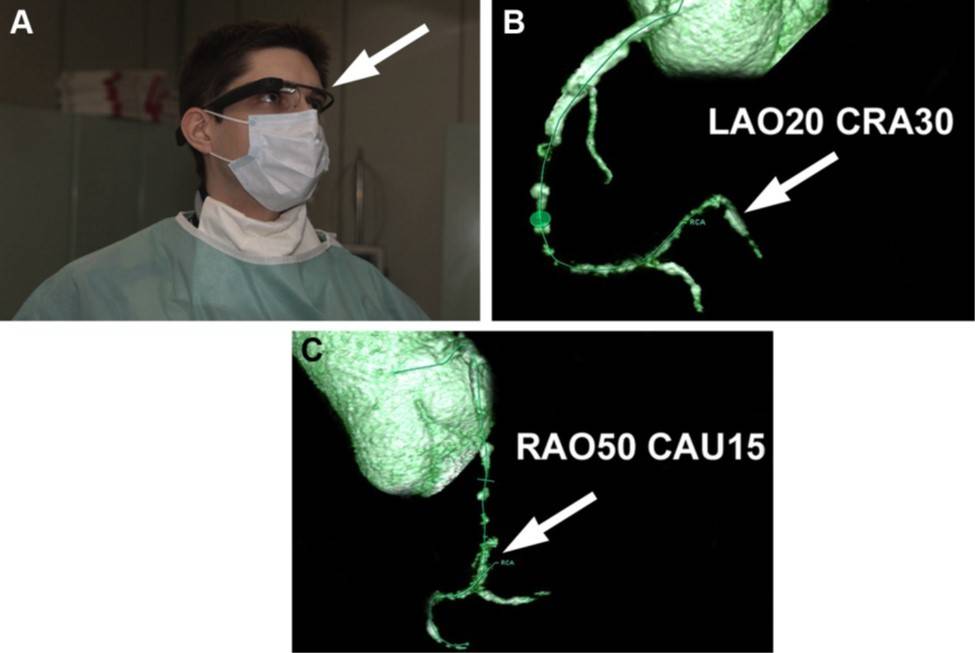

在华沙大学的跨学科中心,研究者们试图通过谷歌眼镜克服这个难题。谷歌眼镜能够将 CTA 的数据直接反馈给术者,帮助可视化阻塞支,并指导导丝运行方向(图 A-C,动画 1-2)。最终,他们成功在一位 49 岁的男性上实现了这项技术。并同时置入 2 枚支架。这在世界上尚属首次。

图:谷歌眼镜下的手术视野。A:术者在术中通过眼镜右上方观看 CTA 结果(箭头)。B、C:谷歌眼镜直接显示了右冠状动脉远端阻塞的三维图像